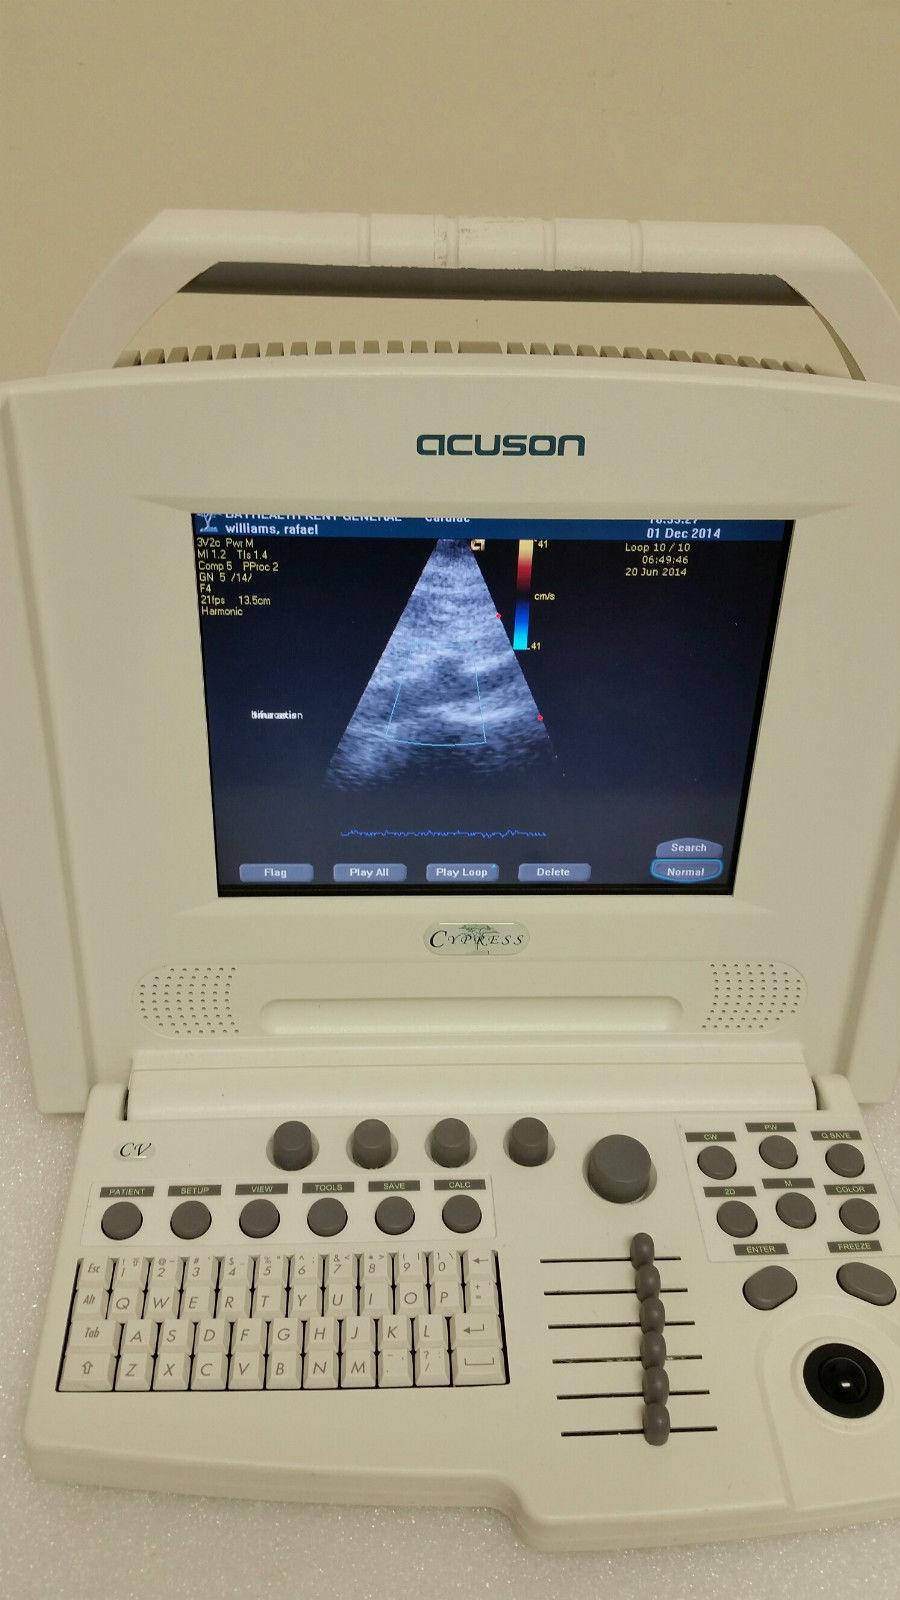

Explore the Acuson Cypress Cardiac Vascular Ultrasound Machine

Seller Notes:âExcellent condition, see photos.â

The Acuson Cypress Cardiac Vascular Ultrasound Machine is engineered for exceptional imaging and diagnostic accuracy. Its advanced technology allows for detailed visualization of cardiac and vascular structures, which is essential for healthcare providers. The inclusion of the 3V2c and 7L3 probes enhances its versatility, making it suitable for various clinical applications. As a result, this machine is a crucial tool in modern cardiology and vascular assessment.

Enhanced User Experience

With a user-friendly interface, the Acuson Cypress simplifies the entire operation process. Health professionals can navigate through its features effortlessly, thanks to the intuitive design and layout. This ease of use not only speeds up the workflow but also improves the overall user satisfaction. Therefore, healthcare practitioners spend less time on technicalities and more on patient care and diagnostics.

Robust and Reliable Performance

Designed for durability and efficiency, the Acuson Cypress guarantees reliable performance in fast-paced clinical environments. Its robust features withstand rigorous daily use while maintaining high-quality imaging standards. Additionally, the machine's consistent performance over time helps healthcare facilities reduce unexpected downtime and maintain patient trust. Thus, investing in the Acuson Cypress is a smart decision for any medical institution aiming for excellence in diagnostics.